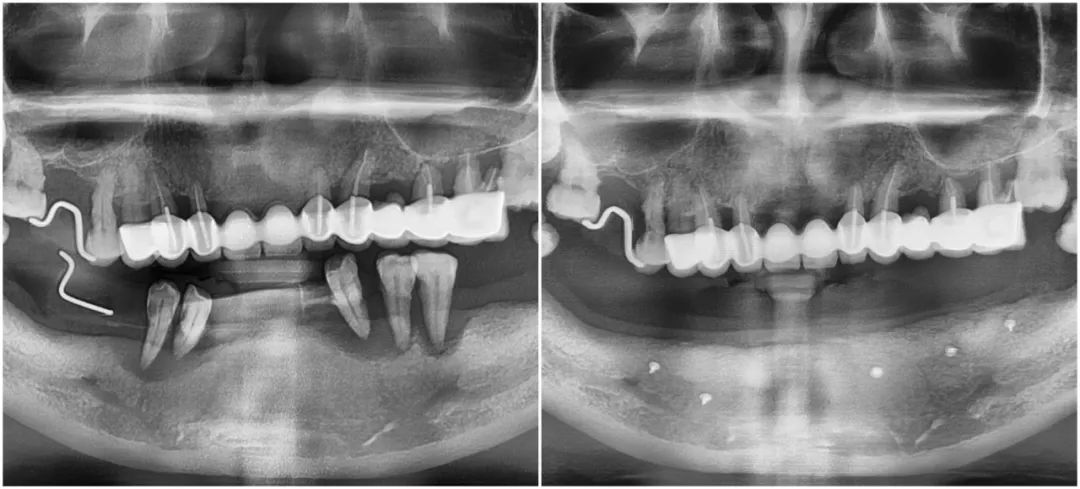

史阿姨下頜拔牙植骨前與拔牙植骨后全景片對比